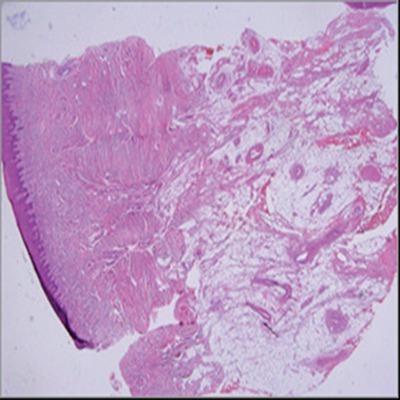

An arteriovenous malformation (AVM) is composed of abnormal communications between arteries and veins without the normal intervening capillary bed. AVM of the head and neck is a rare vascular anomaly. We present here an unusual case of AVM with the size of 4x3 cm at the left posterior palatal area. Incisionel biopsy revealed AVM. Resection of the lesion following angiography was suggested to the patient however, he refused the treatment. The patient was considered to be under control. AVM should always be kept in mind in the differential diagnosis of palatal swellings.

动静脉畸形(AVM)由动脉与静脉之间的异常交通组成,其间无正常的毛细血管床。头颈部动静脉畸形是一种罕见的血管异常。我们在此呈现一例不寻常的动静脉畸形病例,位于左侧腭后区域,大小为4×3厘米。切开活检显示为动静脉畸形。血管造影后建议患者切除病变,然而,他拒绝了治疗。该患者被认为病情得到控制。在腭部肿胀的鉴别诊断中应始终考虑到动静脉畸形。